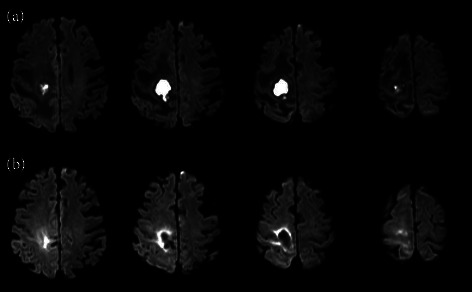

Focal muscle vibration (FMV) is increasingly being recognized as a rehabilitative therapy for enhancing motor function in central nervous system (CNS) diseases, particularly in patients with fine motor control deficits stemming from CNS damage. Brain lesions from these diseases disrupt the motor networks, necessitating novel rehabilitation strategies. By applying vibrations to muscles, FMV stimulates sensory fibers to induce cortical activity and kinesthetic illusions. While initial studies have highlighted FMV's role in reducing spasticity, recent evidence points to its potential in treating motor paralysis. However, prior research has been limited by the lack of acute-phase studies and a focus on patients with minimal muscle contraction capability. This report aimed to explore FMV's efficacy on upper limb motor function in patients with flaccid motor paralysis immediately after acute CNS diseases. We report the case of a septuagenarian male with a brain abscess in the right parietal lobe, leading to flaccid motor paralysis. Rehabilitation included 28 sessions of occupational and physical therapy that incorporated FMV. Significant improvements were observed in upper extremity function, with moderate to very large effect sizes, while lower limb function showed lesser improvement without adverse effects. This case suggests the utility of FMV in enhancing upper-limb motor function after acute CNS injuries, potentially serving as a supplementary therapy for spontaneous recovery. This report contributes to emerging evidence on FMV's benefits in acute flaccid motor paralysis, expanding the documented therapeutic scope.

Abstract Image